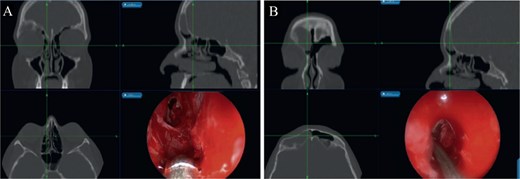

CT scan of the brain and paranasal sinuses in (A) axial and (B) coronal views, showing a lesion in the right frontal sinus with resorption of posterior and lateral walls. The anterior wall shows a depressed fracture.

The patient underwent image-guided ESS with frontal sinusotomy. A 45-angled endoscope helped in recognition of the mucocele, which was treated with marsupialization (Fig. 5). The thick anterior inferior wall was removed. During 2 years of follow-up, no recurrence or complication was observed.

(A) Mucocele Draf IIa wide frontal sinusotomy, (B) image-guided wide marsupialization of mucocele.